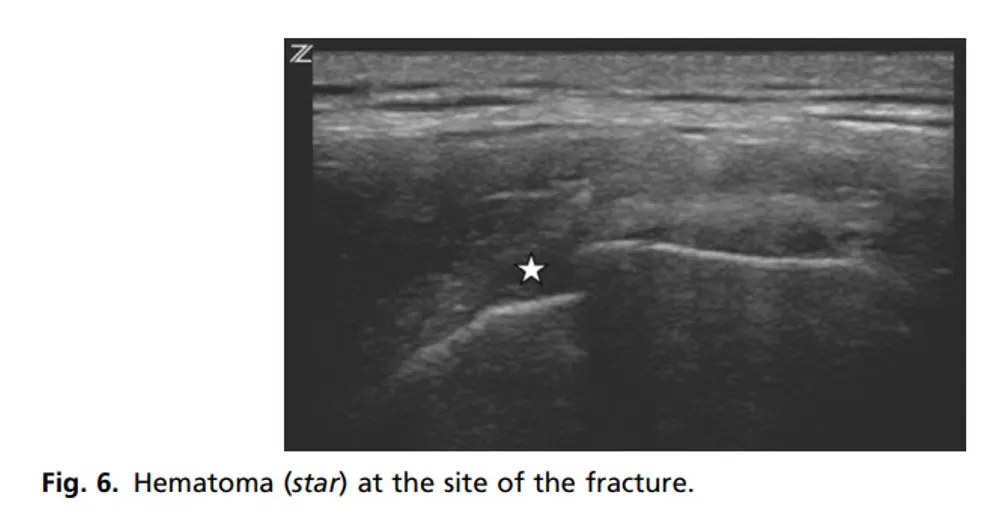

Look for discontinuity

Hematoma of the discontinuity